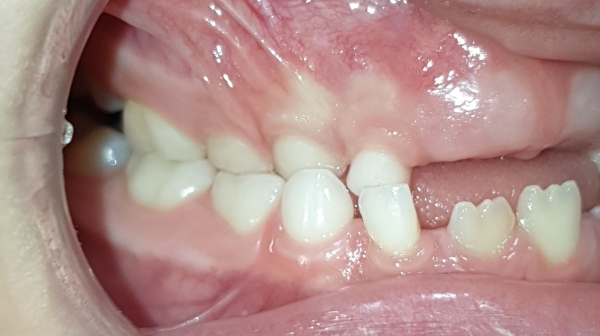

DESPUÉS